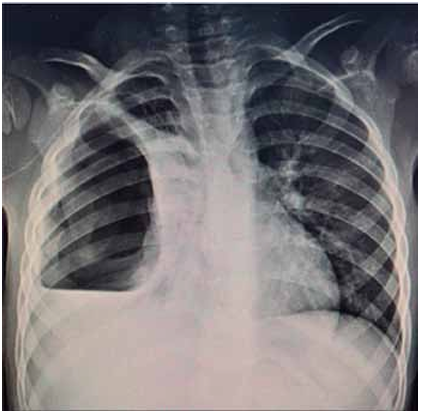

Paciente de 6 anos com quadro de febre alta há 1 semana (máximo de 40 ºC), tosse produtiva, dor torácica e desconforto respiratório progressivo. Ao exame físico, apresentava ausculta reduzida em todo hemitórax direito, com percussão hipertimpânica em terços médio e superior e maciça em terço inferior. Hemitórax esquerdo sem alterações de propedêutica pulmonar. Solicitada radiografia de tórax a seguir.

(Arquivo pessoal; imagem usada com autorização)

Com base nos dados apresentados, assinale a alternativa que descreve o diagnóstico mais provável para o caso.